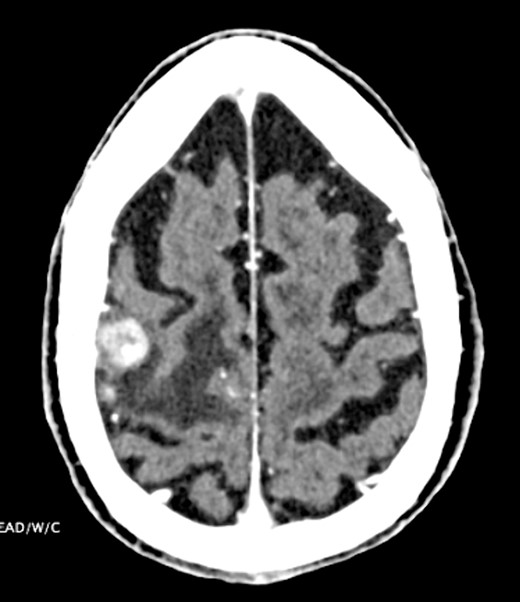

Six months later, the patient had an episode of left-sided focal motor seizure. CT head showed a 1.3-cm heterogeneously enhancing mass lesion with the right frontal lobe motor cortex (Fig. 3). Follow-up MRI-brain revealed several well-defined enhancing nodular lesions within the right frontal lobe predominantly in the region of the pericentral gyrus, the largest of which measured 1.8 cm. The whole body PET-CT showed focal intense activity in the left frontal lobe of the brain corresponding to the area seen on CT and MRI. The patient was started on levetiracetam, dexamethasone, high-dose methotrexate and rituximab. He was treated with high-dose methotrexate and rituximab for presumed recurrence of non-Hodgkin’s lymphoma with plans for three cycles followed by repeat MRI.

CT head indicating 1.3-cm right frontal lobe motor cortex heterogeneously enhancing lesion.

Treatment strategies for PVRL range from systemic high-dose methotrexate, chemotherapy adjunct with stem-cell transplant, and single-agent treatments like ibrutinib, lenalidomide and temozolomide [4]. In this case, intraocular rituximab was initially employed to target CD20-positive B cells within the eye. However, the systemic progression of DLBCL, as evidenced by pleural and pericardial effusions and later CNS involvement, necessitated high-dose methotrexate and rituximab to address CNS disease burden, underscoring the aggressive nature of the disease and the challenges in achieving disease control (Figs 2 and 3).